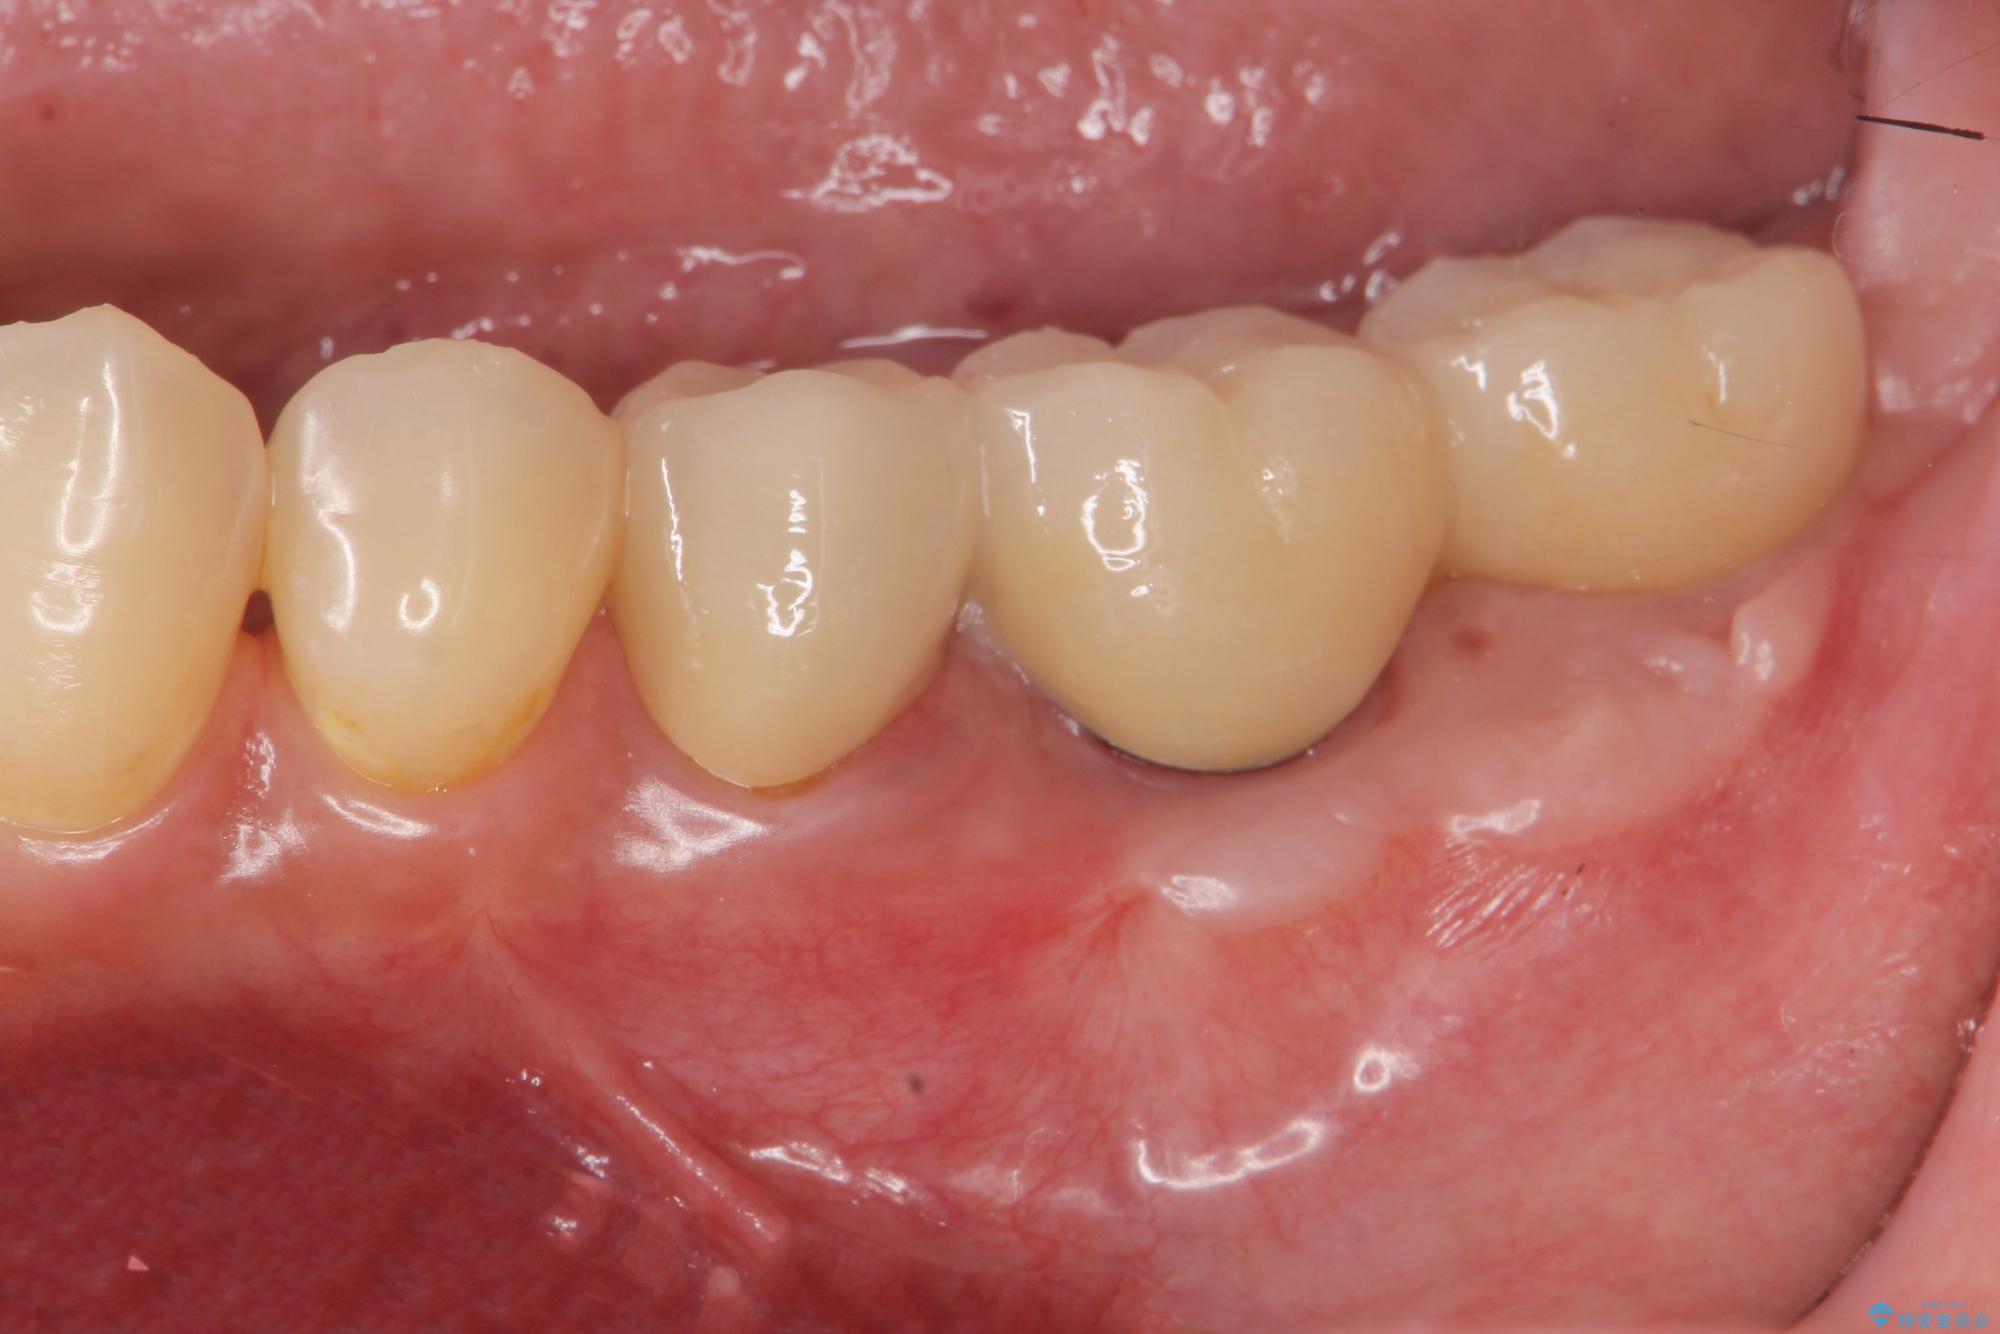

抜歯後、インプラントを用いて咬合機能を回復すると共に周囲に強固な角化歯肉を移植することによりより長期にわたり安定したインプラント周囲環境となるよう治療を計画します。

インプラント周囲の角化歯肉が存在することにより、歯ブラシがしやすくなりインプラントにトラブルが起きる確率を減らしより長期的な予後を望むことができます。